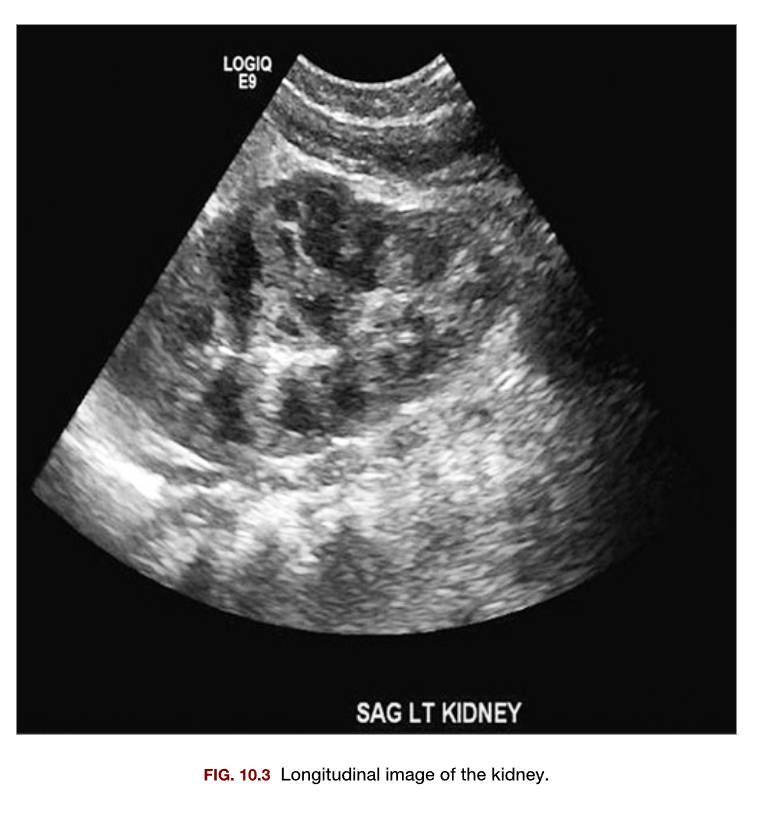

Which of the following conditions is most likely demonstrated in this sonogram of the kidney?

A

1. Hydronephrosis